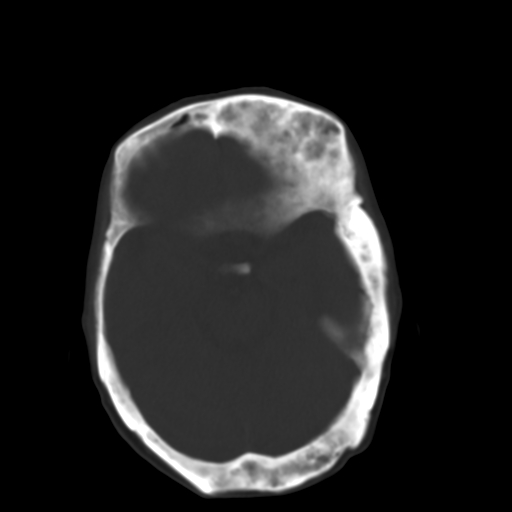

标题: CT17003:F58Y,骨纤维异常增殖征 [打印本页]

标题: CT17003:F58Y,骨纤维异常增殖征

女58y 头晕就诊

左侧额骨增厚,板障层密度增高。 支持骨纤维异常增殖症  。

符合颅骨骨纤维异常增殖症表现。